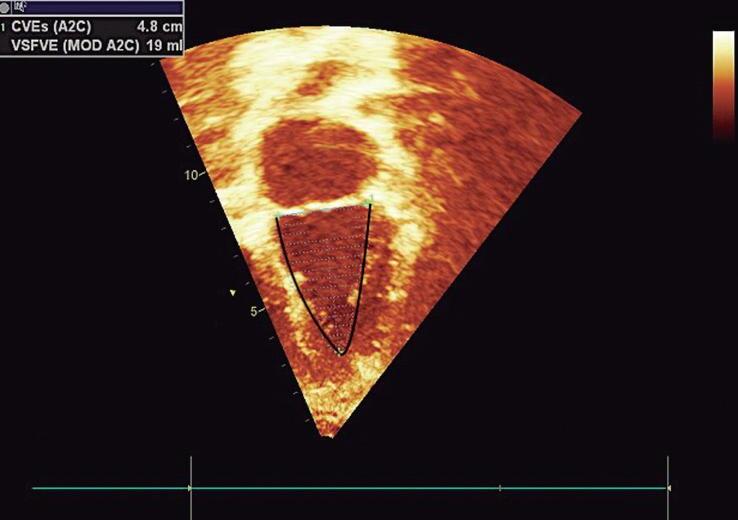

O plano apical eixo longo “2 câmaras” é importante para quantificar o tamanho do AE (volume) e a função sistólica ventricular esquerda (global e segmentar). A contratilidade global do VE pode ser avaliada qualitativamente e quantitativamente pela mensuração dos seus volumes na telessístole e telediástole para cálculo da fração de ejeção pelo método Simpson (conforme detalhado no Capítulo 3) (▶ Vídeo 1-30). Esse plano pode ser obtido, partindo do apical 4 câmaras, pela rotação do transdutor no sentido anti-horário, em aproximadamente 60° (posição equivalente às 12-13 h do relógio) (Figs. 1-5c, 1-11b e 1-12b). Importante: a parede anterior do VE no plano “2 câmaras” estará posicionada à direita da imagem na tela do aparelho de ecocardiografia e a sua parede inferior estará à esquerda.